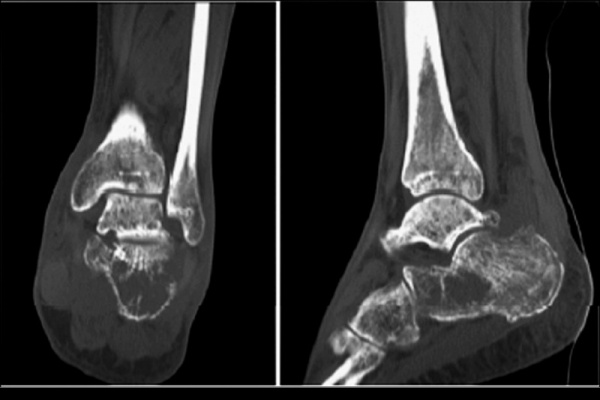

骨骼/脊椎疾病

健康網》關節卡卡不只姿勢問題! 醫點名4大護骨食物

健康網》50歲後最怕不是老 醫警:輕忽「這件事」恐讓失能提早找上門